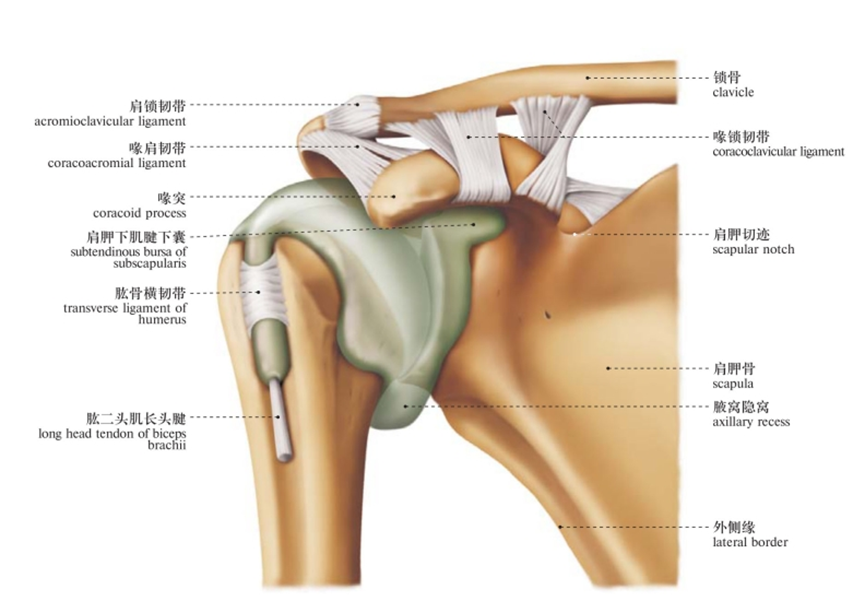

图3 肩关节滑液囊(前面观)

唯有囊下部无韧带和肌加强,最为薄弱,故肩关节脱位是,肱骨头常从下部脱出,脱向前下方。

关节面大小相差较大,关节囊薄弱松弛,连接它约有三条韧带和肌腱,三角肌包裹在肩峰的三面。

3.肱骨横韧带:

为肱骨的固有韧带,横跨结节间沟的上方,有固定肱二头肌长头腱于结节间沟的作用。